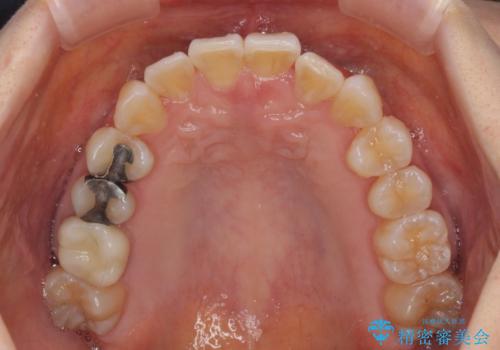

前歯のクロスバイト インビザライン矯正で改善

- むし歯治療を契機に、長年気にしていた前歯のクロスバイトの改善を希望された患者様です。

汚れが溜まりやすく、歯ぎしりがうまくできないため、インビザラインを用いて矯正治療を行うこととしました。

インビザラインによる前歯のクロスバイトの改善は、治療期間中に前歯でしか咬めない時期が続いたり、歯肉退縮や歯髄壊死のリスクが高まったりと、治療中にトラブルを抱えることがあります。

特に上顎側切歯(真ん中から2番目の歯)が舌側に引っ込んでいるケースは、インビザラインでは改善しきれないことがあると言われています。